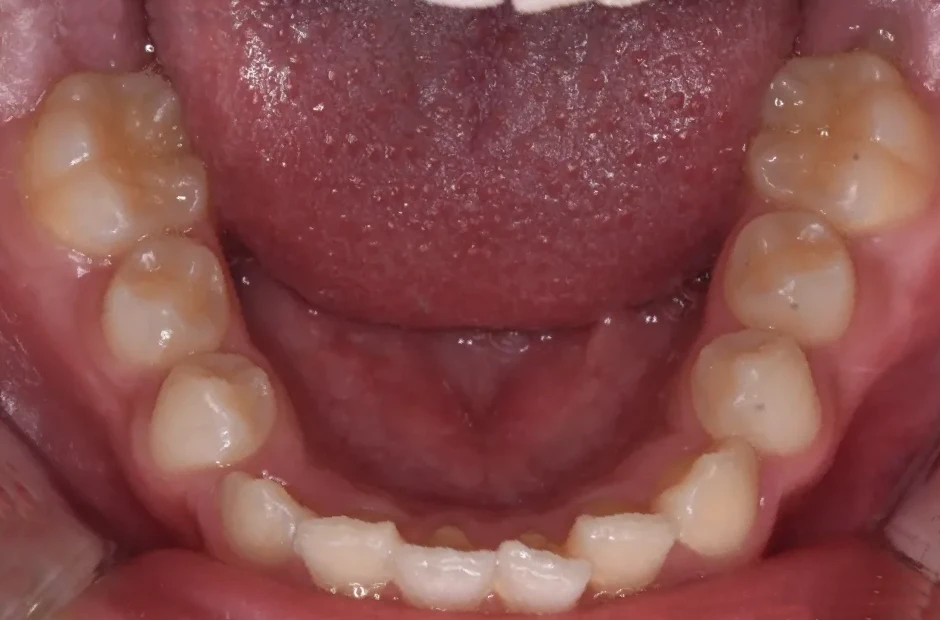

反対咬合

| 診断名・主訴 | 前歯反対咬合 |

|---|---|

| 年齢・性別 | 12歳・男性 |

| 治療期間・回数 | 1年半 18回 |

| 治療に用いた主な装置 | リンガルアーチ(前方誘導弾線) |

| 抜歯部位 | なし |

| 治療費 | 35万円(税抜) |

| リスク・副作用 | 装置による違和感・疼痛・歯肉退縮・歯根吸収・虫歯のリスクなど |